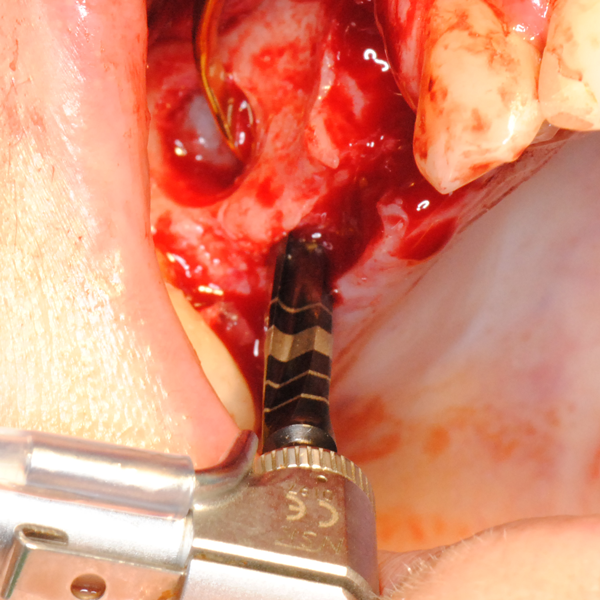

Отворен максиларен синус в началото на интервенцията. Случаят е интересен със следното - твърде атипична форма на трепанационния отвор. На какво се дължи на това - на лошо планиране на оперативния достъп или на нещо друго? Дължи се на факта, че отначало въпросната намеса беше планирана като балонен синуслифт; за съжаление обаче мембраната на синуса се разкъса и надуването на балона стана невъзможно.